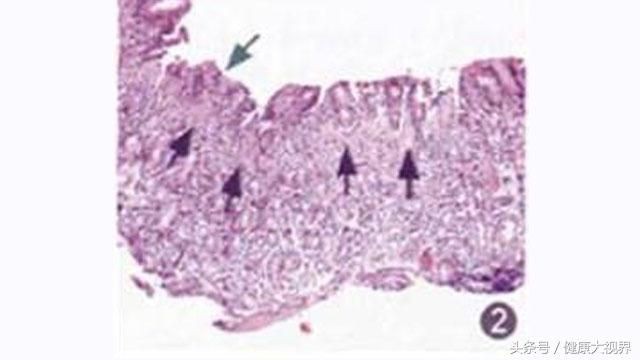

慢性胃炎是一种由复杂原因造成的胃粘膜慢性炎症。这种胃病在镜下有黏膜萎缩性改变,但还没达到萎缩性胃炎的诊断标准。

胃黏膜的细胞5-10天就要更换一遍,当机体出现营养不良,细胞生长所需的“材料”不足,或者血液循环受阻,菌毒感染,以及自身激素出现问题时,新细胞生长跟不上老细胞衰亡的速度,胃黏膜就会出现老化、变薄、萎缩,甚至进一步病变恶化。